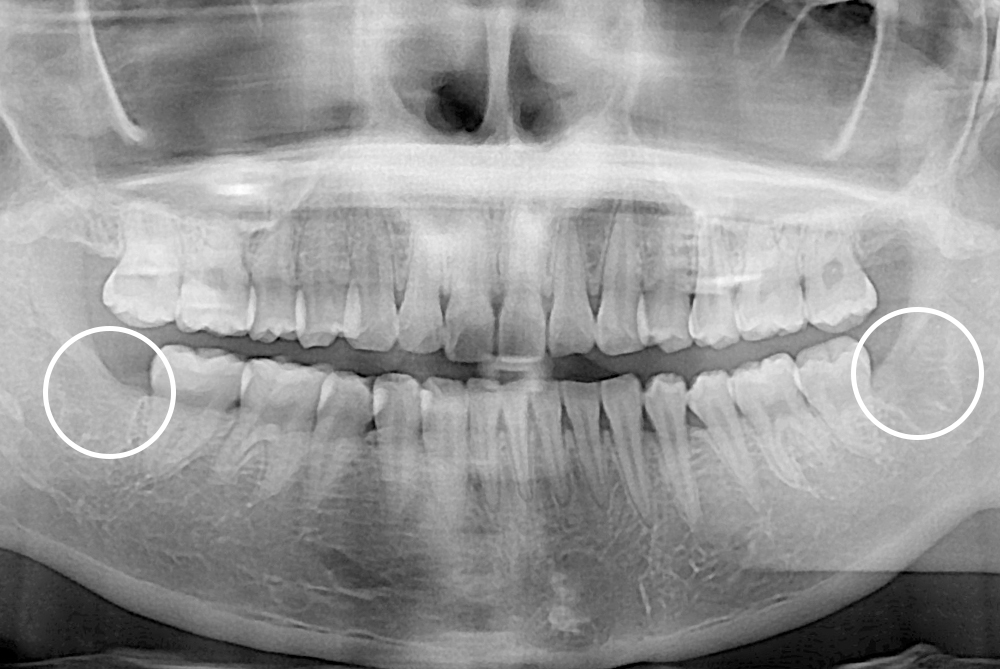

[사랑니] 매복 사랑니 발치

치료전 : 2021-02-13